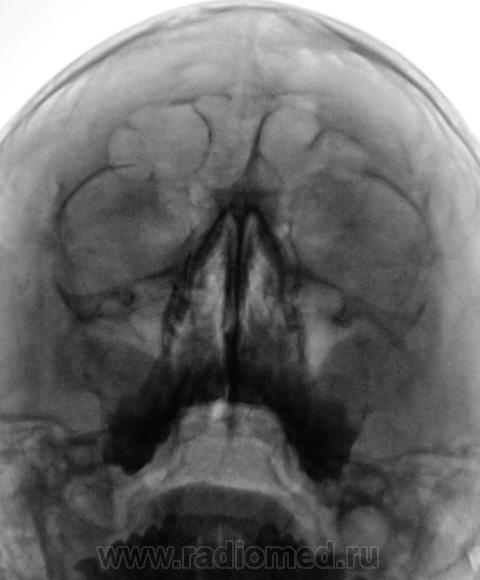

Пациент направлен оториноларингологом на рентгенографию придаточных полостей носа.

Произведено стандартное исследование.

В центральной ячейке лобной пазухи - уровень жидкости - фронтит. в верхнечелюстных пазухах - картна кист, и сфеноидит...

Ячейки решетчатых костей с обеих сторон затемнены, имеются пристеночные теневые наслоения в обеих в/челюстных пазухах, больше у наружных стенок, , с четкими выпуклыми контурами, носовые ходы сужены. R-картина синуита. В наличии горизонтальных уровней в лобных пазухах сомневаюсь. А что бы определиться с основной пазухой, хорошо бы сделать боковую проекцию.

То же склонен видеть уровень жидкости в лобных (видно что повторяет наклон), пристеночное подушкообразное утолщение слизистой в верхнечелюстных, сфеноидит.

Согласна с коллегой по поводу сомнительности затемнения лобных пазух, это может быть обусловлено ячейками решетчатой кости.